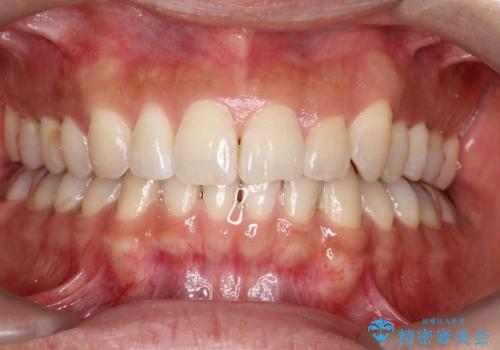

![[ インビザライン矯正 ] マウスピース矯正で治す、前歯のガタつきの症例 治療前](https://seimitsushinbi.jp/wp/wp-content/uploads/2022/02/324533f54aaa29eca08b0a9fdd3af7e2-500x350.jpg?v=1644473292)